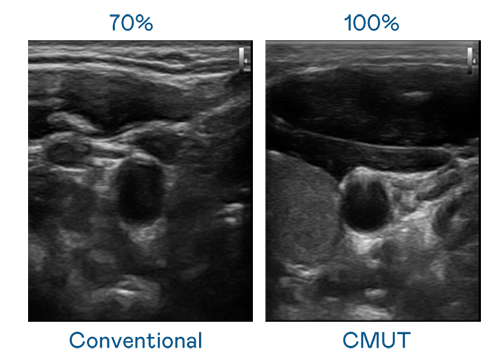

CMUT 技术是一种用电容式微机电元件来产生超音波讯号的技术。与传统 PZT 压电式技术相比,CMUT 频宽增加 30%,更宽频的超音波讯号让影像解析度大幅提升,是实现高影像品质医疗超音波扫描、促进精准医疗发展的关键技术。

超音波影像的解析度高低,首先取决于探头能发出的讯号频宽。BB电子 CMUT 可提供高清晰的超音波讯号,提供高频宽、高灵敏度、影像纹理细节更高的超音波影像,协助医护人员缩短影像判读时间及利用精准的医疗影像进行诊断。